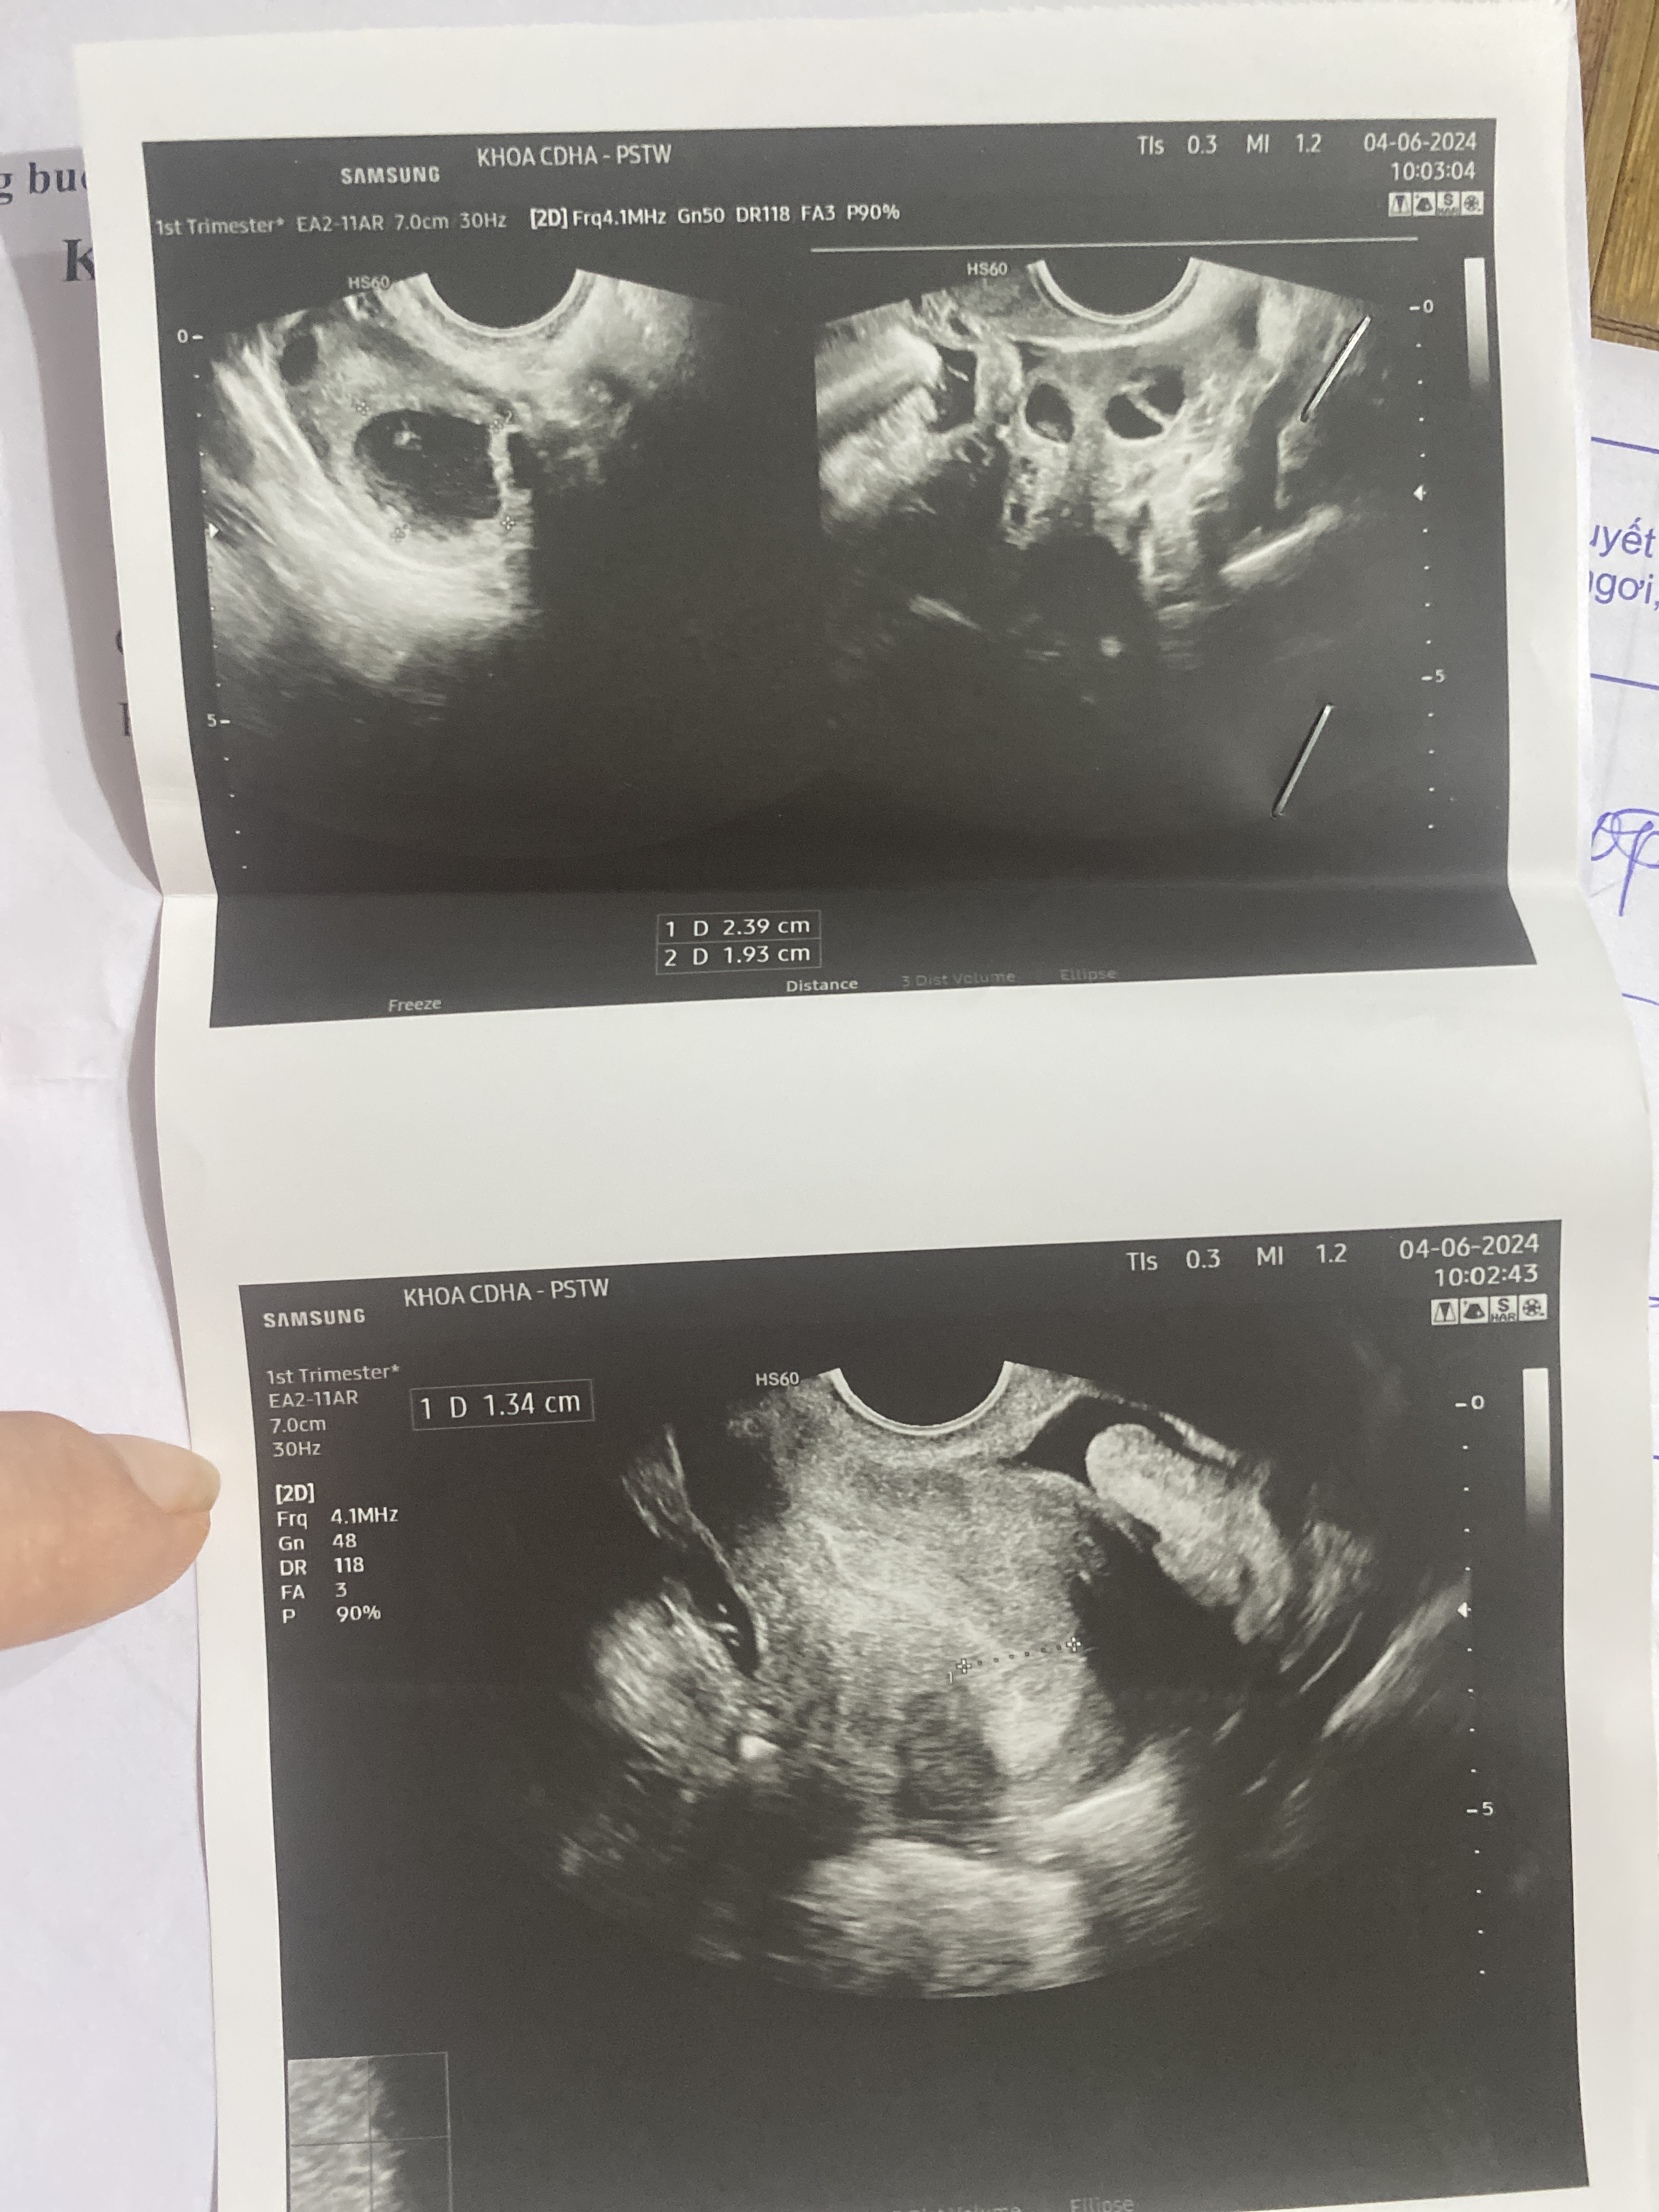

Chào bác sĩ, em tháng nào cũng bị đau bụng kinh dữ dội và đau thắt lưng kéo dài khoảng hơn 3 tiếng trong ngày hành kinh thứ 3. Em thường cứ khom người xuống thì nó sẽ hơi giảm triệu chứng, nhưng không được bao lâu lại đau. Em đi khám sau 10 ngày sạch kinh thì bác sĩ có chuẩn đoán như hình. Bác sĩ cho em hỏi cách điều trị bệnh này với ạ 😭

Em bị tình trạng gọi là thống kinh, siêu âm thấy có nang dịch không đồng nhất - cái này cần đánh giá kỹ hơn xem nang dạng lạc nội mạc, nang xuất huyết hay u bì, u quái… chẩn đoán đúng và đầy đủ rồi mới điều trị em nhé